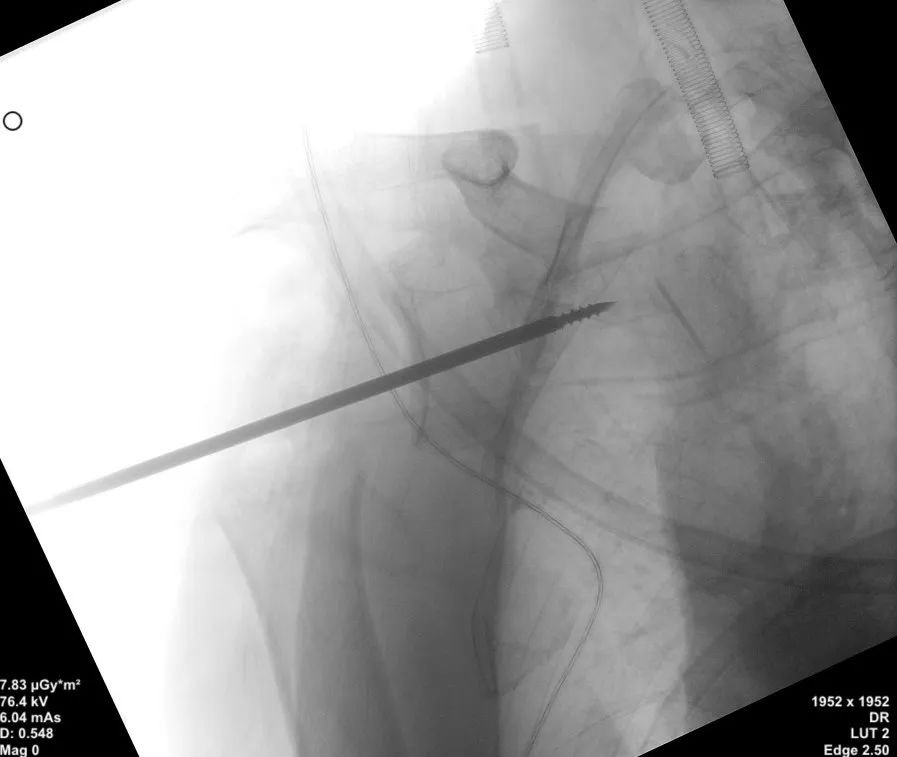

患者沙滩椅体位,手术使用胸肌三角肌入路,充分显露后常规进行肱骨侧和肩盂侧准备,在至关重要的肩盂侧基座导针置入步骤,在锁骨近端安放患者示踪器,使用术中三维影像设备获取肩关节三维图像,扫描结果传输至机器人导航系统,完成路径规划,并在机器人的引导下置入导针,置入后再次进行CT扫描验证,证实导针精确置入,完美符合预期。

术中,导针精准植入。